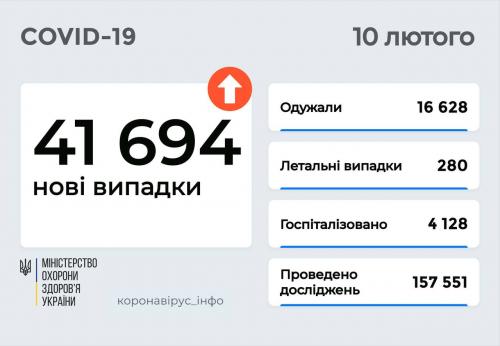

МОЗ: Уперше з початку пандемії було зроблено понад 100 тисяч ПЛР-досліджень за добу